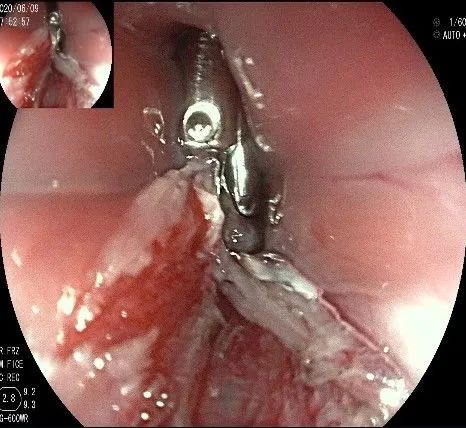

在食管腔内,瘤体的两侧行粘膜下注射后,在瘤体顶部纵向自口侧向肛侧切开食管粘膜。

向下一直切开至齿状线处,白色为鳞状上皮,红色为腺上皮,颗粒样的部分,就是炎性息肉。切开后可见瘤体为白色,表面有血管网,质地较韧。

沿切开的边缘,从口侧开始向下进行粘膜下剥离,剥离的间隙是瘤体之上粘膜之下,期间反复进行粘膜下注射。

随着剥离的进行,瘤体与周围组织的关系越来越清晰。

此时瘤体基底部已暴露出来,起源于固有肌层。

这是最后的“根”部。

换用IT刀可以轻松剥离,又避免切入过深造成穿孔。